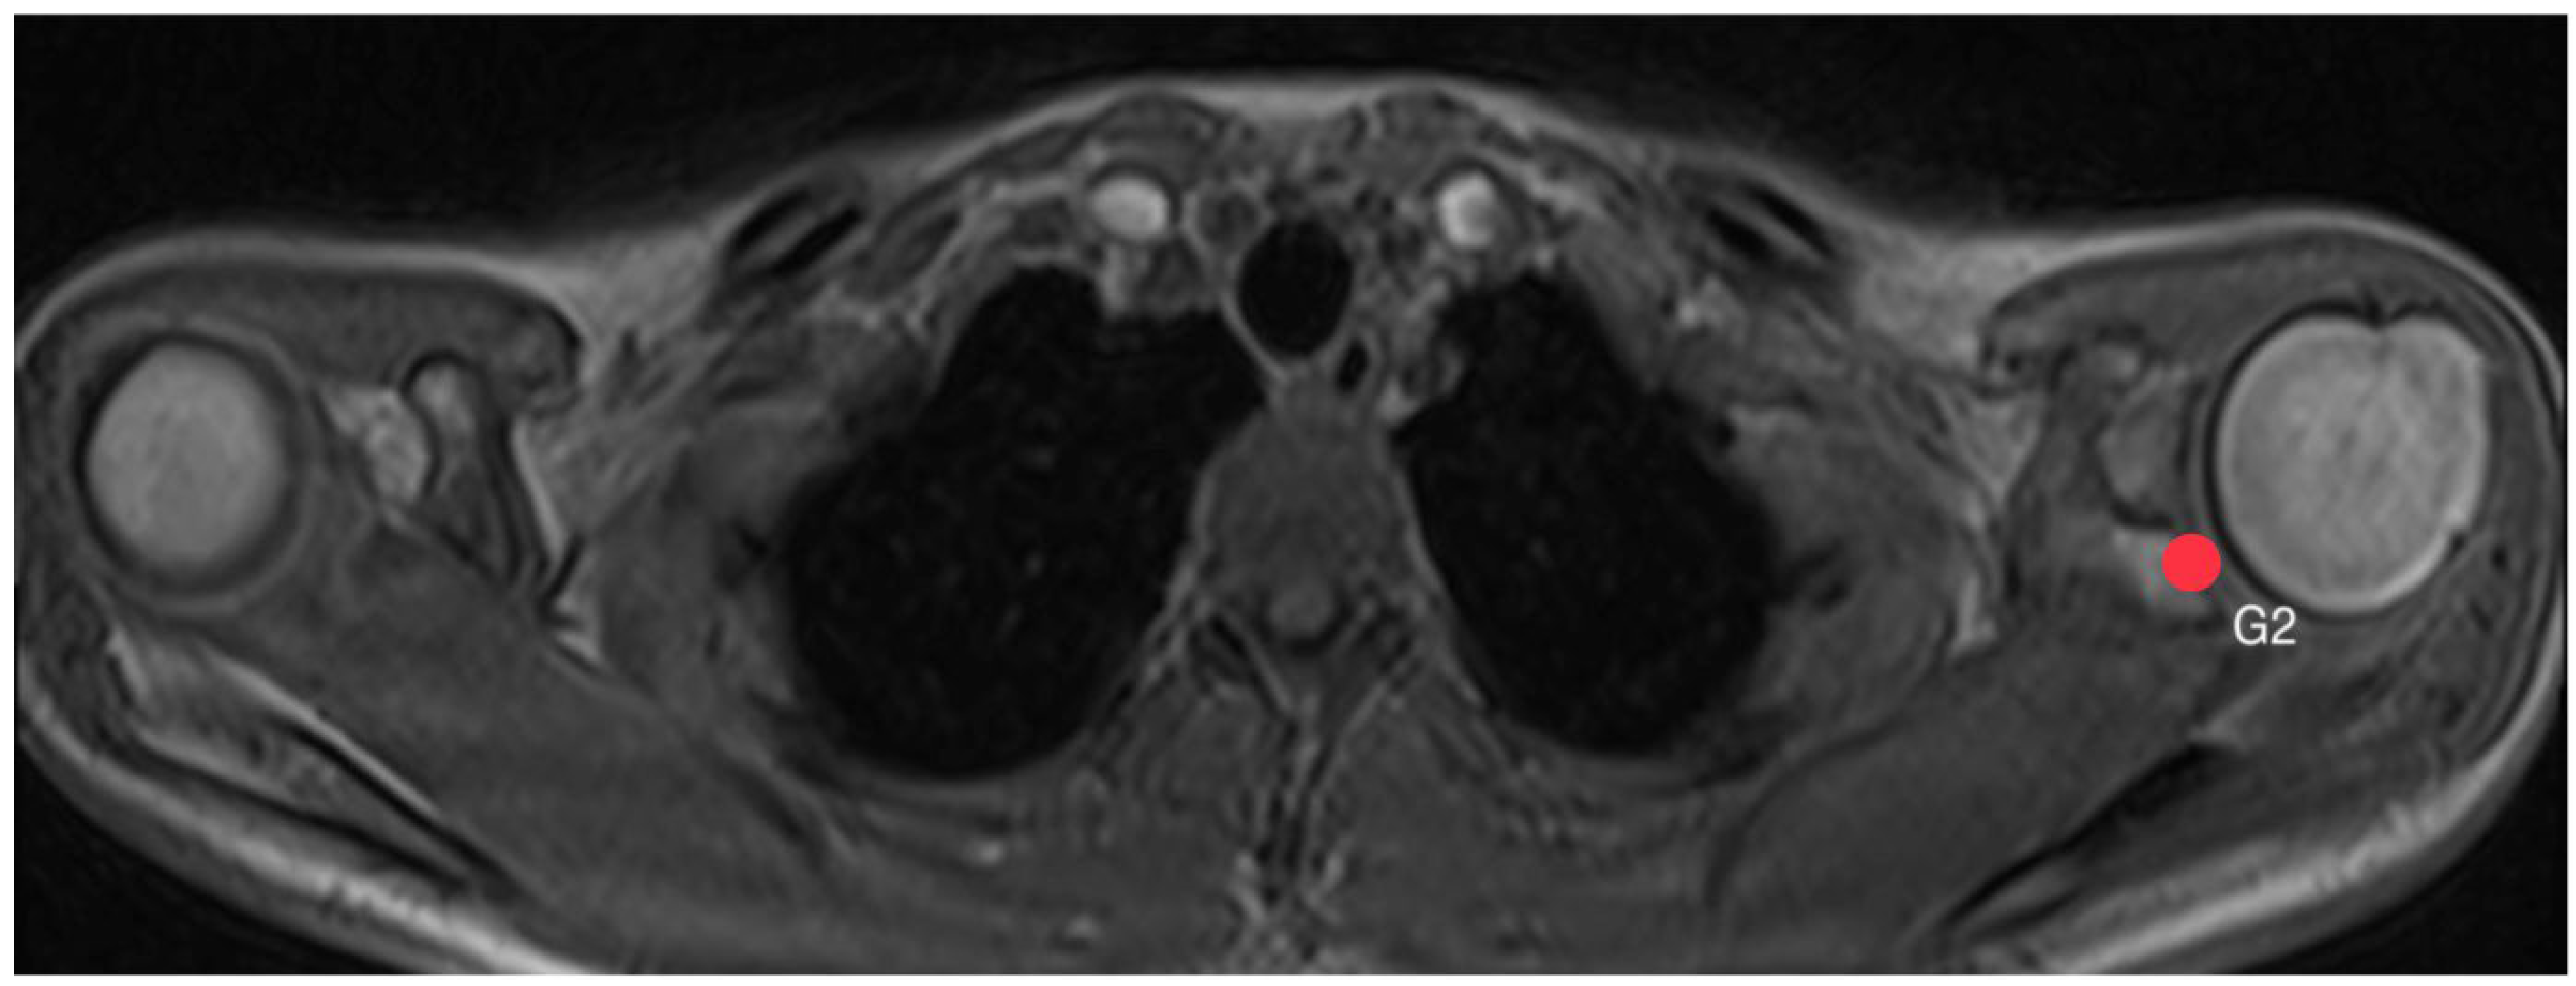

2.4. Acromion Tilt (Figure 6)